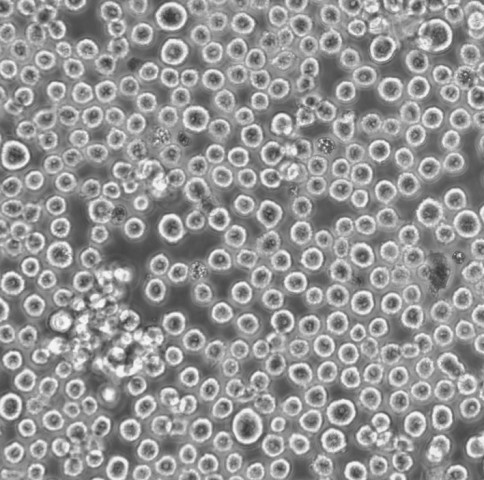

生长特性:悬浮生长

形态特性:淋巴母细胞样

淋巴母细胞(lymphoblast)是一类未成熟的淋巴细胞,通常在淋巴组织的发育过程中出现。它们在淋巴瘤和白血病的病理过程中扮演重要角色。淋巴母细胞是淋巴细胞的前体细胞,处于从造血干细胞向成熟淋巴细胞分化的过程中。它们可以来源于T细胞或B细胞。根据来源不同,淋巴母细胞可分为T细胞淋巴母细胞和B细胞淋巴母细胞。